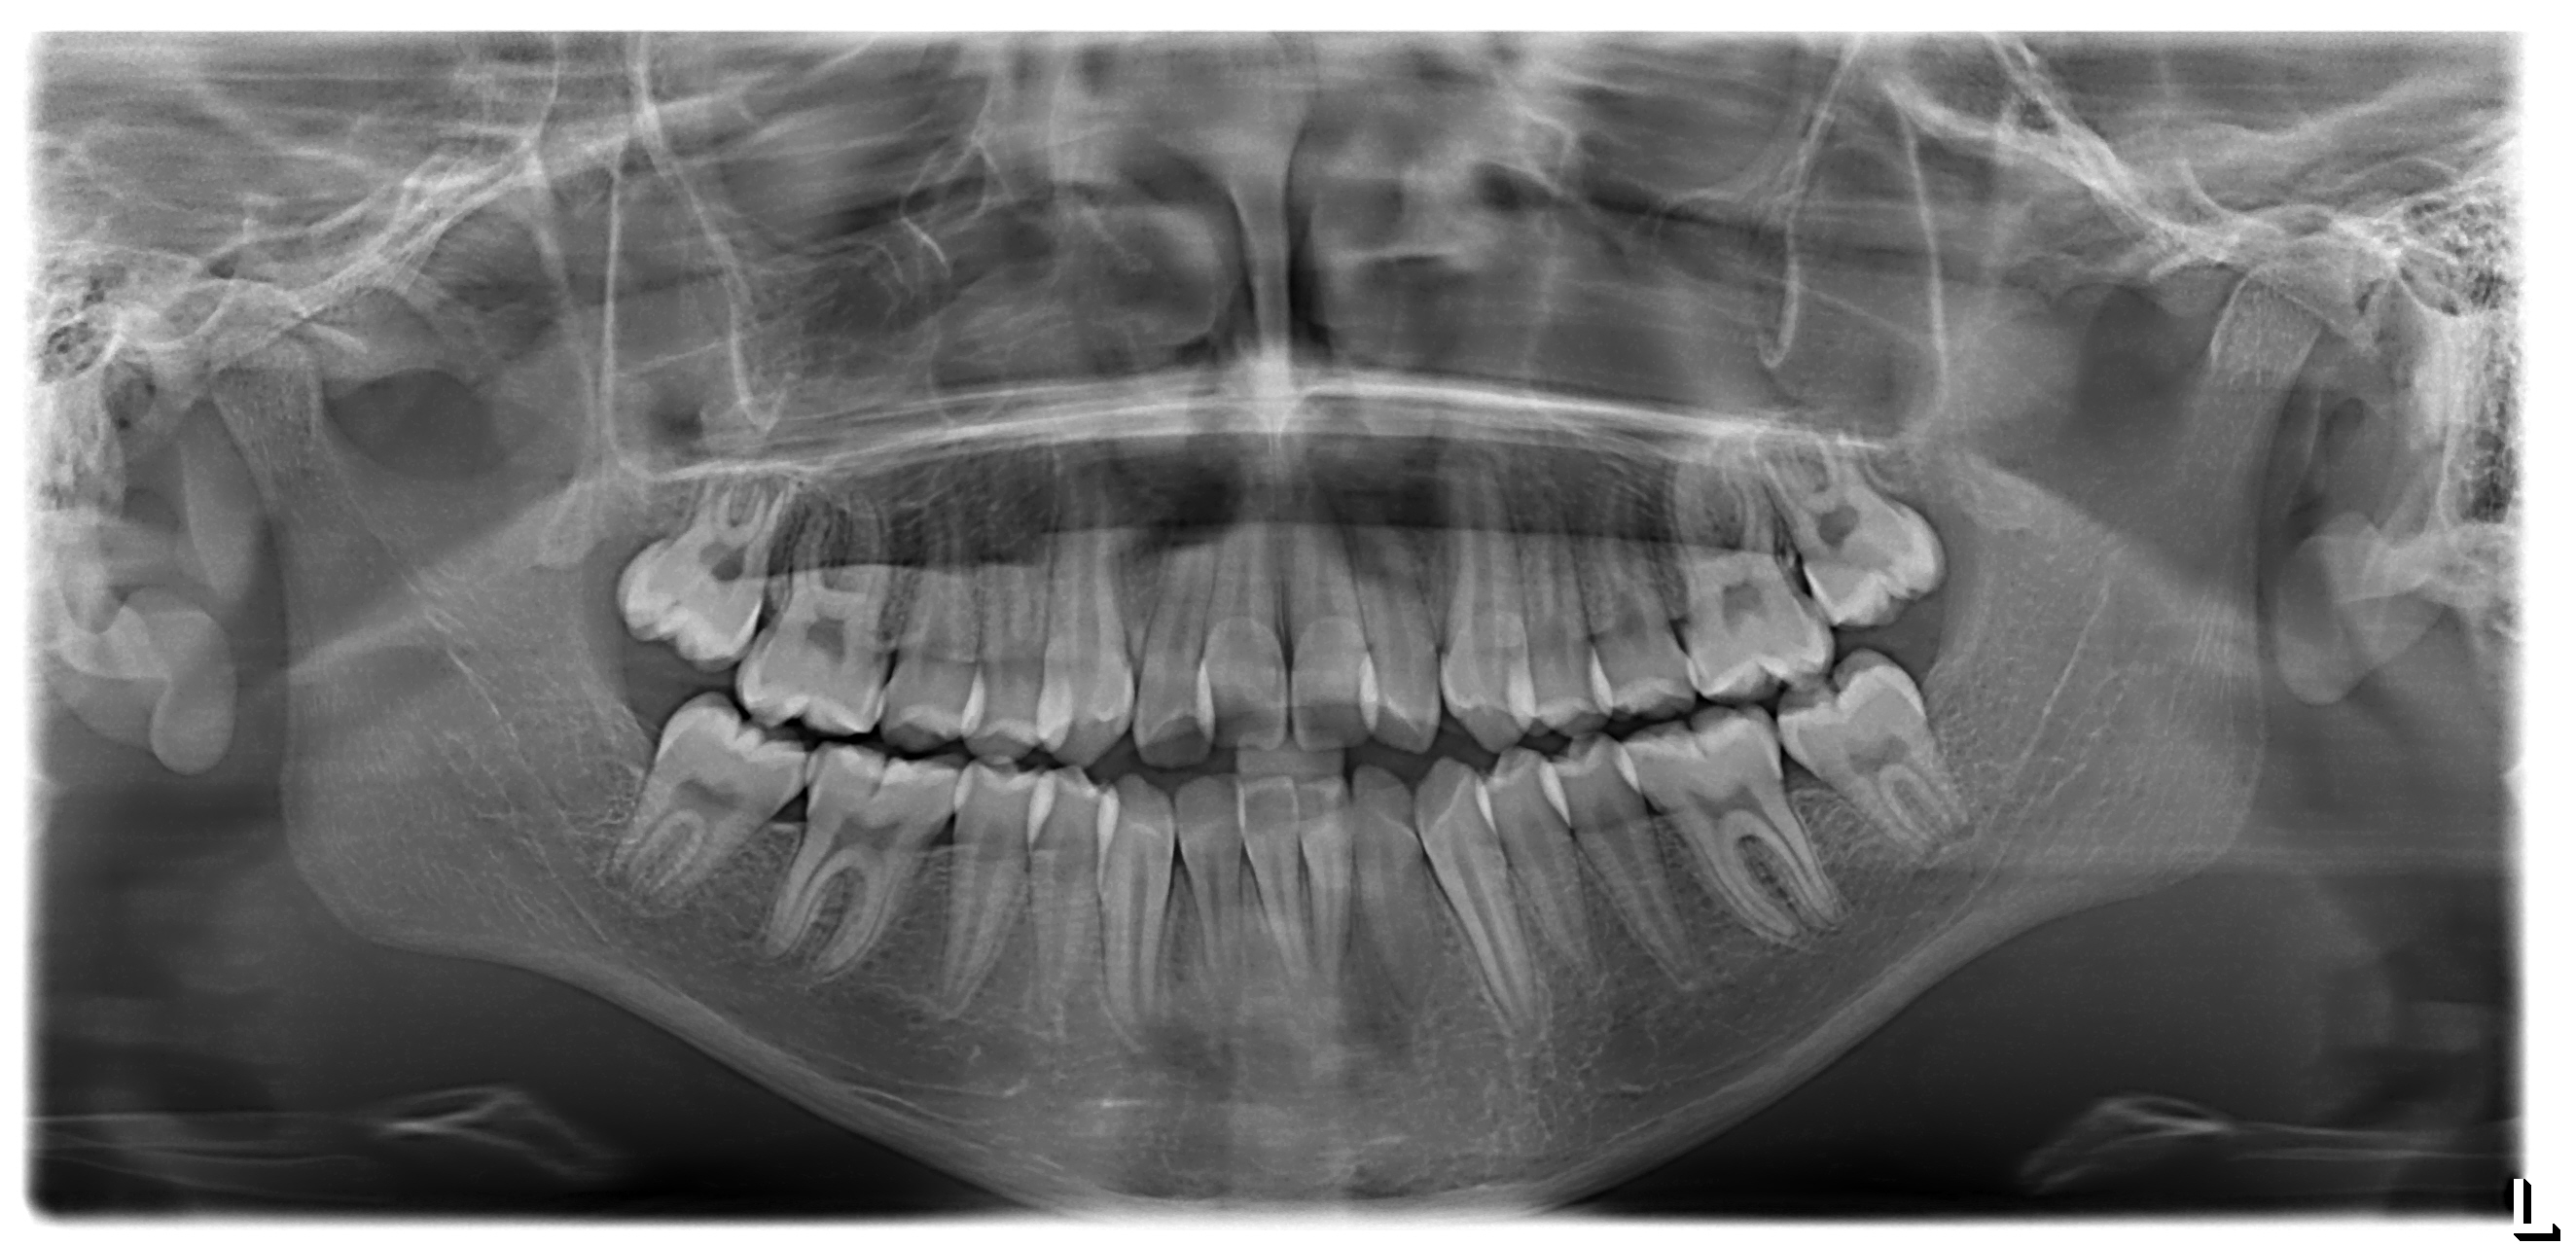

Radiografías Digitales

Tecnología digital avanzada para imágenes instantáneas y de máxima claridad.